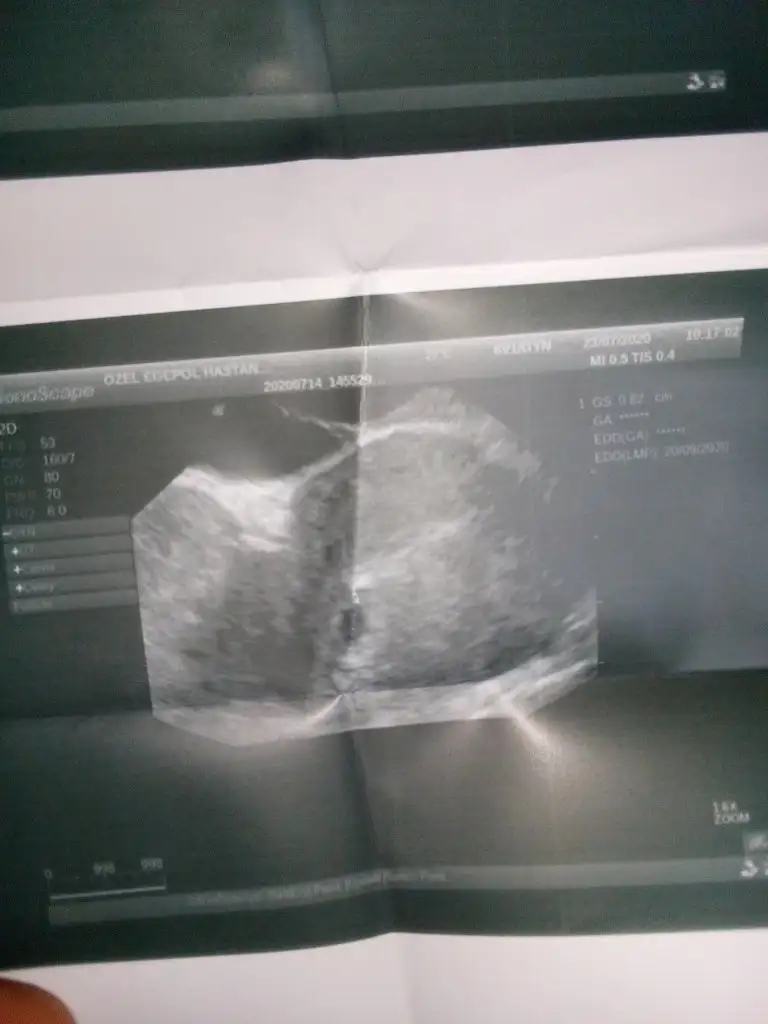

6+3Kese için 6-7-8 olmalı

Buna göre kız gibi en iyi 11 12 13 haftalar olmalıAaaIkra meyra canım seni bu konuda da gördüm genital nub da kimin bebeğini gösterdiysem hepsini doğru bildin :) ilk bebeği ede erkek demiştin oda erkek 3 yaşında şuan:) 2.gebeliğim canım sence keseye göre nedir varmı bi tahminin 6 haftalık şuan :)

Ay canım ağzın bal yesin Allah evlatlrına uzun sağlıklı ömürler versin inşallah :) 11-12 yi bekliyoruz o zaman genital nub için :)Buna göre kız gibi en iyi 11 12 13 haftalar olmalı